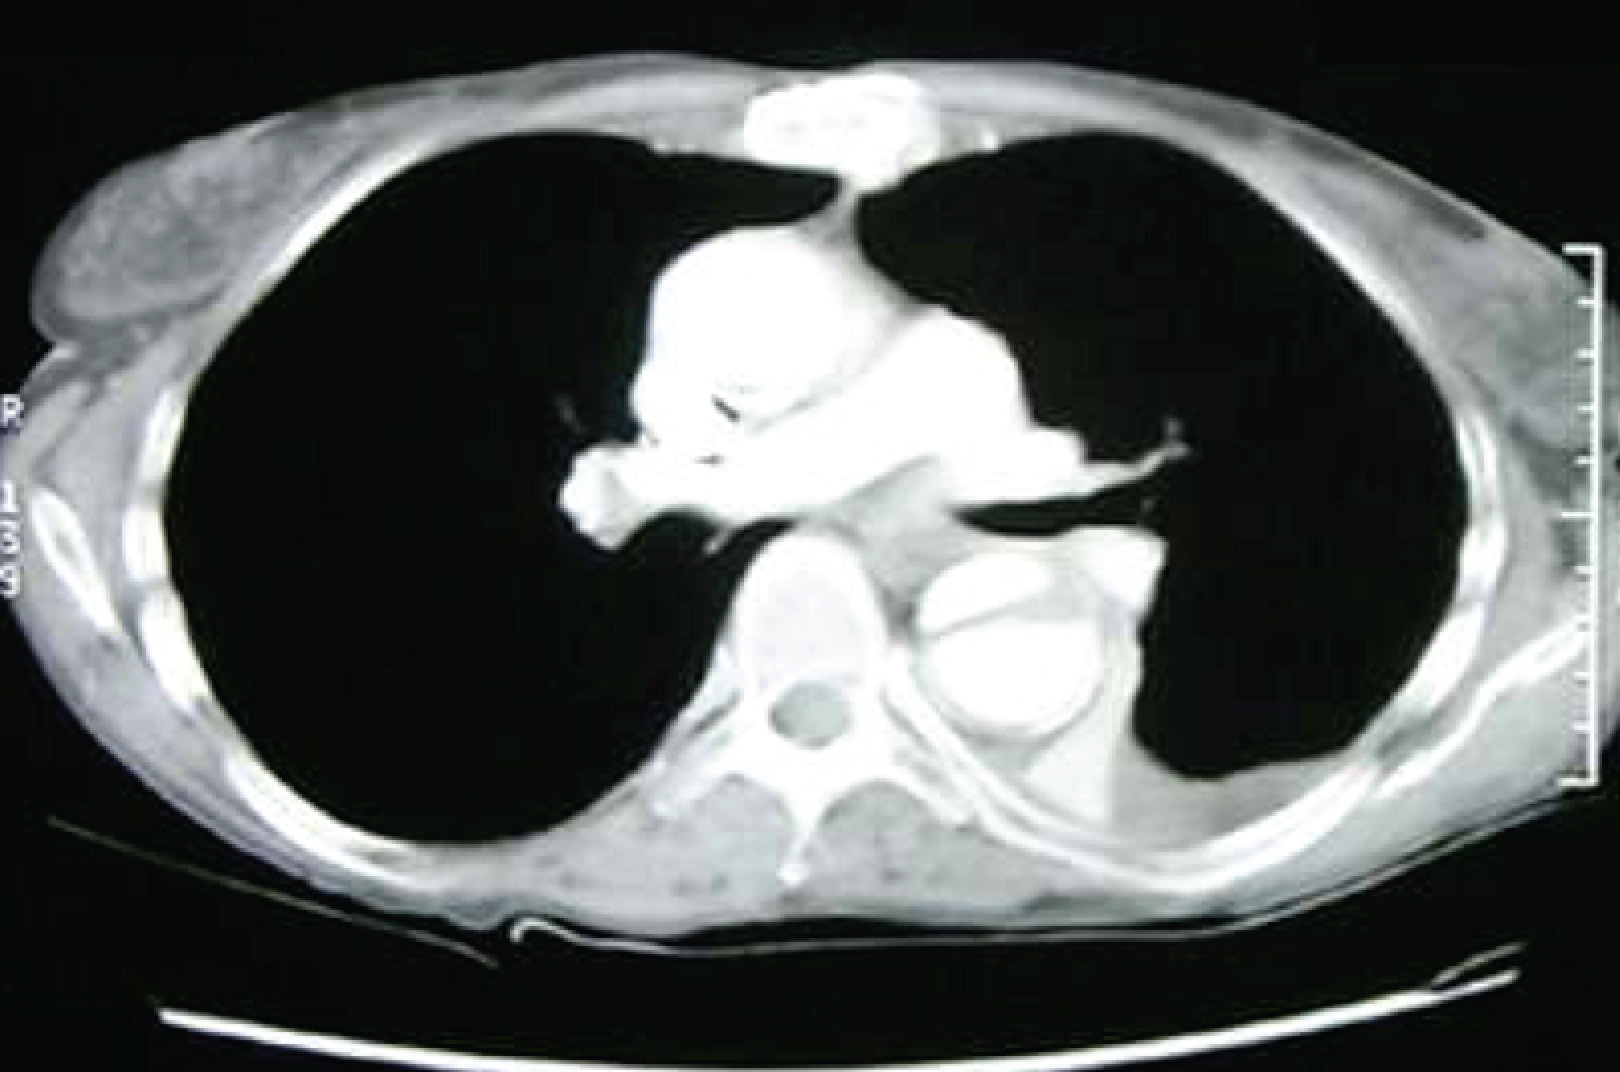

A rather difficult case to guess, perhaps. But this patient had a normal WBC with normal differential counts despite having Gram-negative bacteraemia, and one of the few types of Gram-negative rods where such a phenomenon is observed is Salmonella spp. Given the elderly patient and the aortic dissection seen on the chest X-ray, this is likely non-typhoidal Salmonella bacteraemia with infected aortic aneurysm/dissection. A CT image is shown below.

Management is surgical (as for any aortic dissection) and a prolonged course of antibiotics. There is likely no difference in outcomes between oral and IV antibiotics for the treatment of this condition.